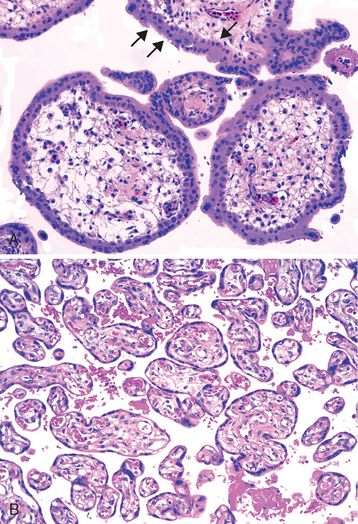

The placenta is composed of chorionic villi (Fig. 22-51) that sprout from the chorion to provide a large contact area between the fetal and maternal circulations. In the mature placenta, the maternal blood enters the intervillous space through endometrial arteries (spiral arteries) and circulates around the villi allowing for gaseous and nutrient exchange (Fig. 22-52). The deoxygenated blood flows back from the intervillous space to the decidua and enters the endometrial veins. Deoxygenated fetal blood enters the placenta through two umbilical arteries that branch radially to form chorionic arteries. Chorionic arteries additionally branch as they enter the villi. In the chorionic villi they form an extensive capillary system, bringing fetal blood in close proximity to maternal blood. The gas and nutrient diffusion occurs through the villous capillary endothelial cells and thinned-out syncytiotrophoblast and cytotrophoblast. Under normal circumstances there is no mixing between the fetal and maternal blood. Blood oxygenated in the placenta returns to the fetus through the single umbilical vein.

image

FIGURE 22-51 A, First-trimester chorionic villi composed of delicate mesh of central stroma surrounded by two discrete layers of epithelium—the outer layer consisting of syncytiotrophoblast (two arrows) and the inner layer consisting of cytotrophoblast (arrow). B, Third-trimester chorionic villi composed of stroma with dense network of dilated capillaries surrounded by markedly thinned-out syncytiotrophoblast and cytotrophoblast (same magnification as A.)